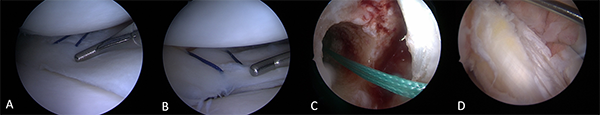

A través de los portales clásicos (anterolateral y anteromedial) se exploró la articulación, procurando identificar lesiones asociadas. En concordancia con estudio previo de RM se corroboró la rotura completa de las fibras del neoLCA de injerto autólogo ST-RI de la primera revisión, la lesión longitudinal en zona roja-blanca de cuerno posterior de menisco medial, la lesión insercional posterior de menisco lateral y moderada sinovitis.

Se efectuó inicialmente la sutura meniscal interna con dos puntos verticales, y luego la sutura de la desinserción posterior del menisco lateral, ambas con técnica fuera-dentro (outside-inside), logrando una correcta reducción y estabilidad de ambos meniscos.

A continuación, la reconstrucción del LCA fue practicada con técnica transportal medial (anatómica), permitiendo cubrir mejor la huella femoral. Se realizó el túnel femoral usando parte del túnel preexistente, comenzando con una mecha de 8 mm, ubicándolo mínimamente más posterior y proximal; luego se utilizó mecha de 9 mm, y a continuación dilatador de 9-10 mm. A nivel tibial, se empleó el mismo túnel preexistente en su totalidad, trabajándolo con mecha de 8 mm en un principio, y luego con la de 9 mm, concluyéndolo al igual que el túnel femoral con dilatador de 9-10 mm para compactar bien el hueso esponjoso. Se introdujo el nuevo injerto autólogo cuadricipital según técnica conocida, y nueva fijación con dos tornillos biocompuestos (Biocomposite-Arthrex® original) de 8x23 mm y 9x23 mm, se constató buena isometría y tensión (fig. 5).

Figura 5: Visión artroscópica. A) Sutura meniscal interna con dos puntos verticales. B) Sutura meniscal externa con dos puntos verticales. C) Túnel femoral. D) Plástica de re-revisión con autoinjerto cuadricipital.